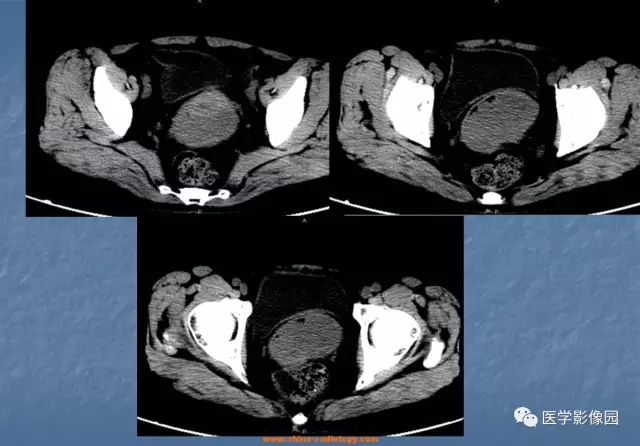

【病例】宫颈癌1例CT影像表现

诊断结果:宫颈鳞癌